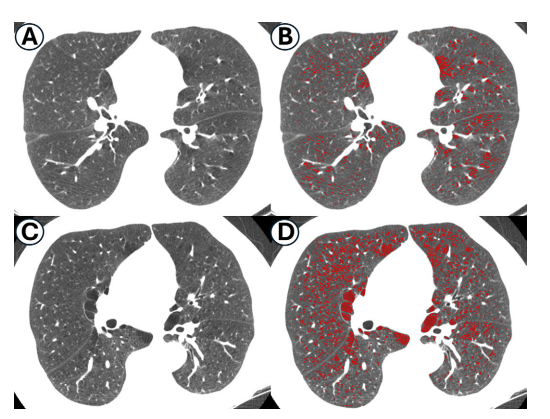

Figure 4: Axial CT images in participants with (A, B) nonprogression and (C, D) progression of emphysema. Those with progression of emphysema show increased “compactness” of CT emphysema voxels (red) compared with those without progression of emphysema. Normalized join-count (NJC) and lung density (LD) values are as follows: (A, B) NJC = 0.18, LD = 47 g/L; (B, C) NJC = 0.57, LD = 38 g/L. Images are shown at a window level of −800 HU and window width of 800 HU.

图4:参与者的轴向CT图像中显示(A,B)肺气肿无进展和(C,D)肺气肿进展。与无进展者相比,肺气肿进展者显示出CT肺气肿体素(红色)的“紧凑性”增加。归一化连接计数(NJC)和肺密度(LD)值如下:(A,B)NJC = 0.18,LD = 47 g/L;(B,C)NJC = 0.57,LD = 38 g/L。图像显示在-800 HU的窗位和800 HU的窗宽下。